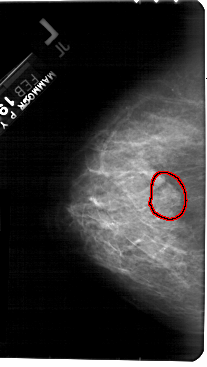

A_1397_1.LEFT_CC

LEFT_CC LINES 5491 PIXELS_PER_LINE 3091 BITS_PER_PIXEL 12 RESOLUTION 43.5 OVERLAY

FILE: A_1397_1.LEFT_CC.OVERLAY

TOTAL_ABNORMALITIES 1

ABNORMALITY 1

LESION_TYPE MASS SHAPE LOBULATED MARGINS OBSCURED

ASSESSMENT 4

SUBTLETY 3

PATHOLOGY BENIGN

TOTAL_OUTLINES 1

BOUNDARY